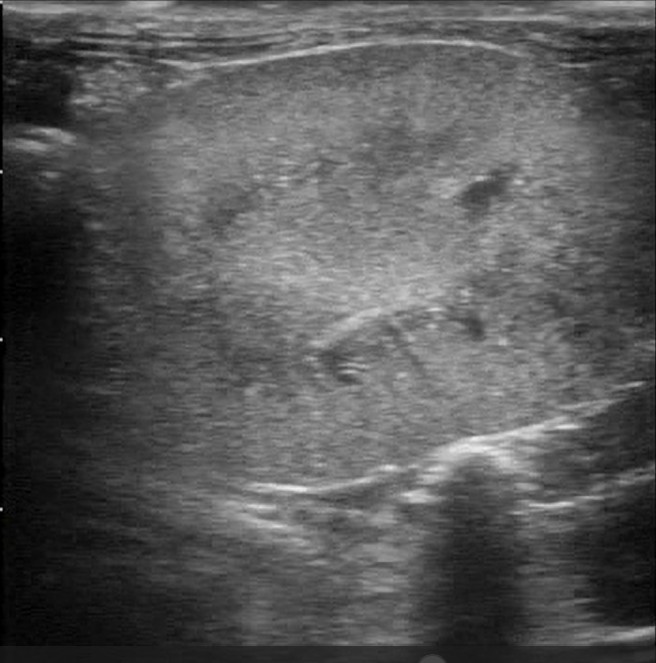

超音波検査

ウサギの腎不全において、超音波検査は、腎臓の大きさに加え、X線検査では評価が困難な腎実質の内部構造、皮質と髄質の境界、腎盂の状態、さらには血流(ドップラー使用時)を評価するために不可欠な診断ツールです。CRFが進行すると、腎臓は線維化や組織の萎縮により縮小(腎萎縮)し、正常より小さくなることがあります 。また、腎臓の辺縁が不整になり、ゴツゴツとした輪郭を呈することがあります 。間質の線維化、尿細管変性、鉱質沈着(石灰化)などが起こると、腎実質(特に皮質)のエコー輝度は上昇し、周囲の脾臓や肝臓と比較して白っぽく見えます 。急性腎不全では、浮腫や炎症の程度によってエコー輝度が低下することもあります 。正常なウサギでは、皮質(やや低エコー)と髄質(より低エコー)の境界は比較的明瞭に描出されます 。慢性腎不全で線維化や実質の構造破壊が進行すると、この皮質・髄質境界は不明瞭になります 。腎石灰化によるカルシウム沈着は、高エコー輝度の斑点や線状構造として描出され、強い音響陰影を伴うことがあります。また、水腎症では腎盂内部が無エコーの尿で拡張する一方、腎盂膿瘍では無エコーよりエコー輝度が高い膿によって拡張します。腎実質内に辺縁明瞭な無エコー領域(嚢胞)が単発性または多発性(多発性嚢胞腎)に見られることもあります 。腎臓腫瘤は、腎臓の形状不整、実質の不均一なエコーパターン、あるいは正常構造を破壊する腫瘤(例:リンパ腫によるびまん性の高エコーまたは低エコー浸潤)として観察されることがあります。